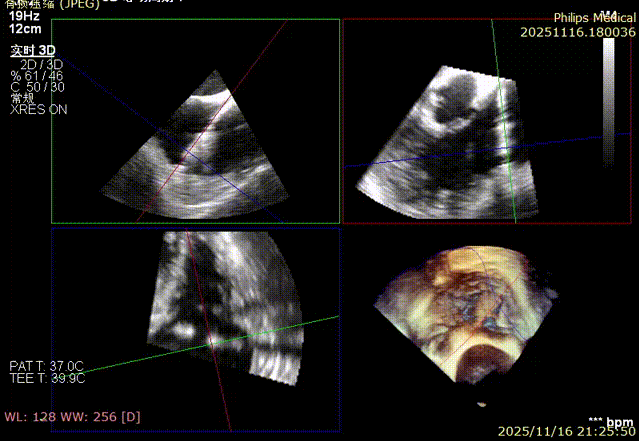

K-Clip® Tricuspid Annuloplasty (Seamless Transition):Immediately after LAAC, the operators established a new vascular access route and advanced the K-Clip® delivery system directly into the right atrium, targeting the posterior-septal and anterior-posterior commissures of the tricuspid annulus. Under real-time ultrasound guidance, the team precisely anchored, clipped, and released the devices.

2.Advancement of the steerable large sheath and delivery system under ultrasound guidance.

3.Steering and rotating the delivery system to target the site while engaging the anchor screw via the 3D MPR plane.

4.Opening the clip arms, adjusting orientation, landing, and closing the clip.

6.Repeating the process for the second clip: steering, rotating, targeting, and engaging the anchor screw.

7.Opening arms, adjusting orientation, landing, and closing the second clip.

8.Right coronary angiography confirming no impact on the RCA before releasing the second implant.